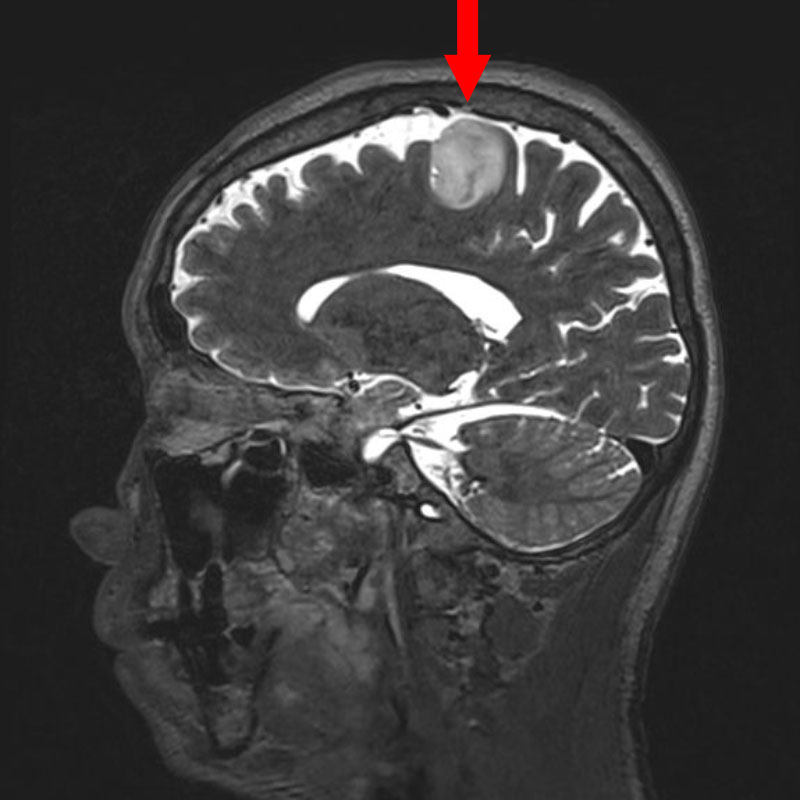

No.’25_37 手術前1

No.’25_37 手術前2